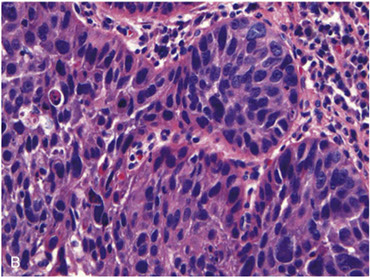

SCC composed of nests of malignant cells that partially recapitulate the organization of squamous epithelium